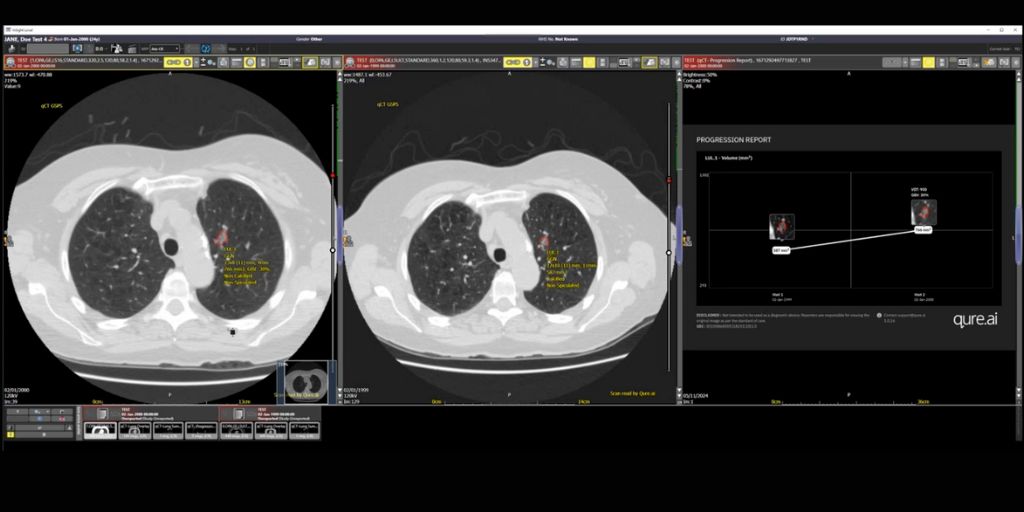

Tej Pandher, a Consultant Radiologist at University Hospitals Plymouth NHS Trust states, “Lung nodule AI assistance helps to identify and track suspicious nodules over time. The reporting radiologist can then put any such nodules into a clinical context and provide useful information for further follow up and/or treatment.”

“qCT has been designed to provide clinical decision support in the detection, characterisation, quantification and monitoring of lung nodules. It can also pull patient images from prior examinations to provide comprehensive nodule management and support progression monitoring over time. This makes it easier for the clinician to assess the growth of nodules with standardised data for volumetry assessment and an auto assigned malignancy risk score of pulmonary nodules using the Brock model/ BTS Guidelines,” continues Surabhi Srivastava.

qCT from global healthcare AI innovator Qure.ai, is part of an end-to-end AI-powered lung cancer care continuum suite of solutions for chest X-ray and CT, to detect, measure and track lung nodules.